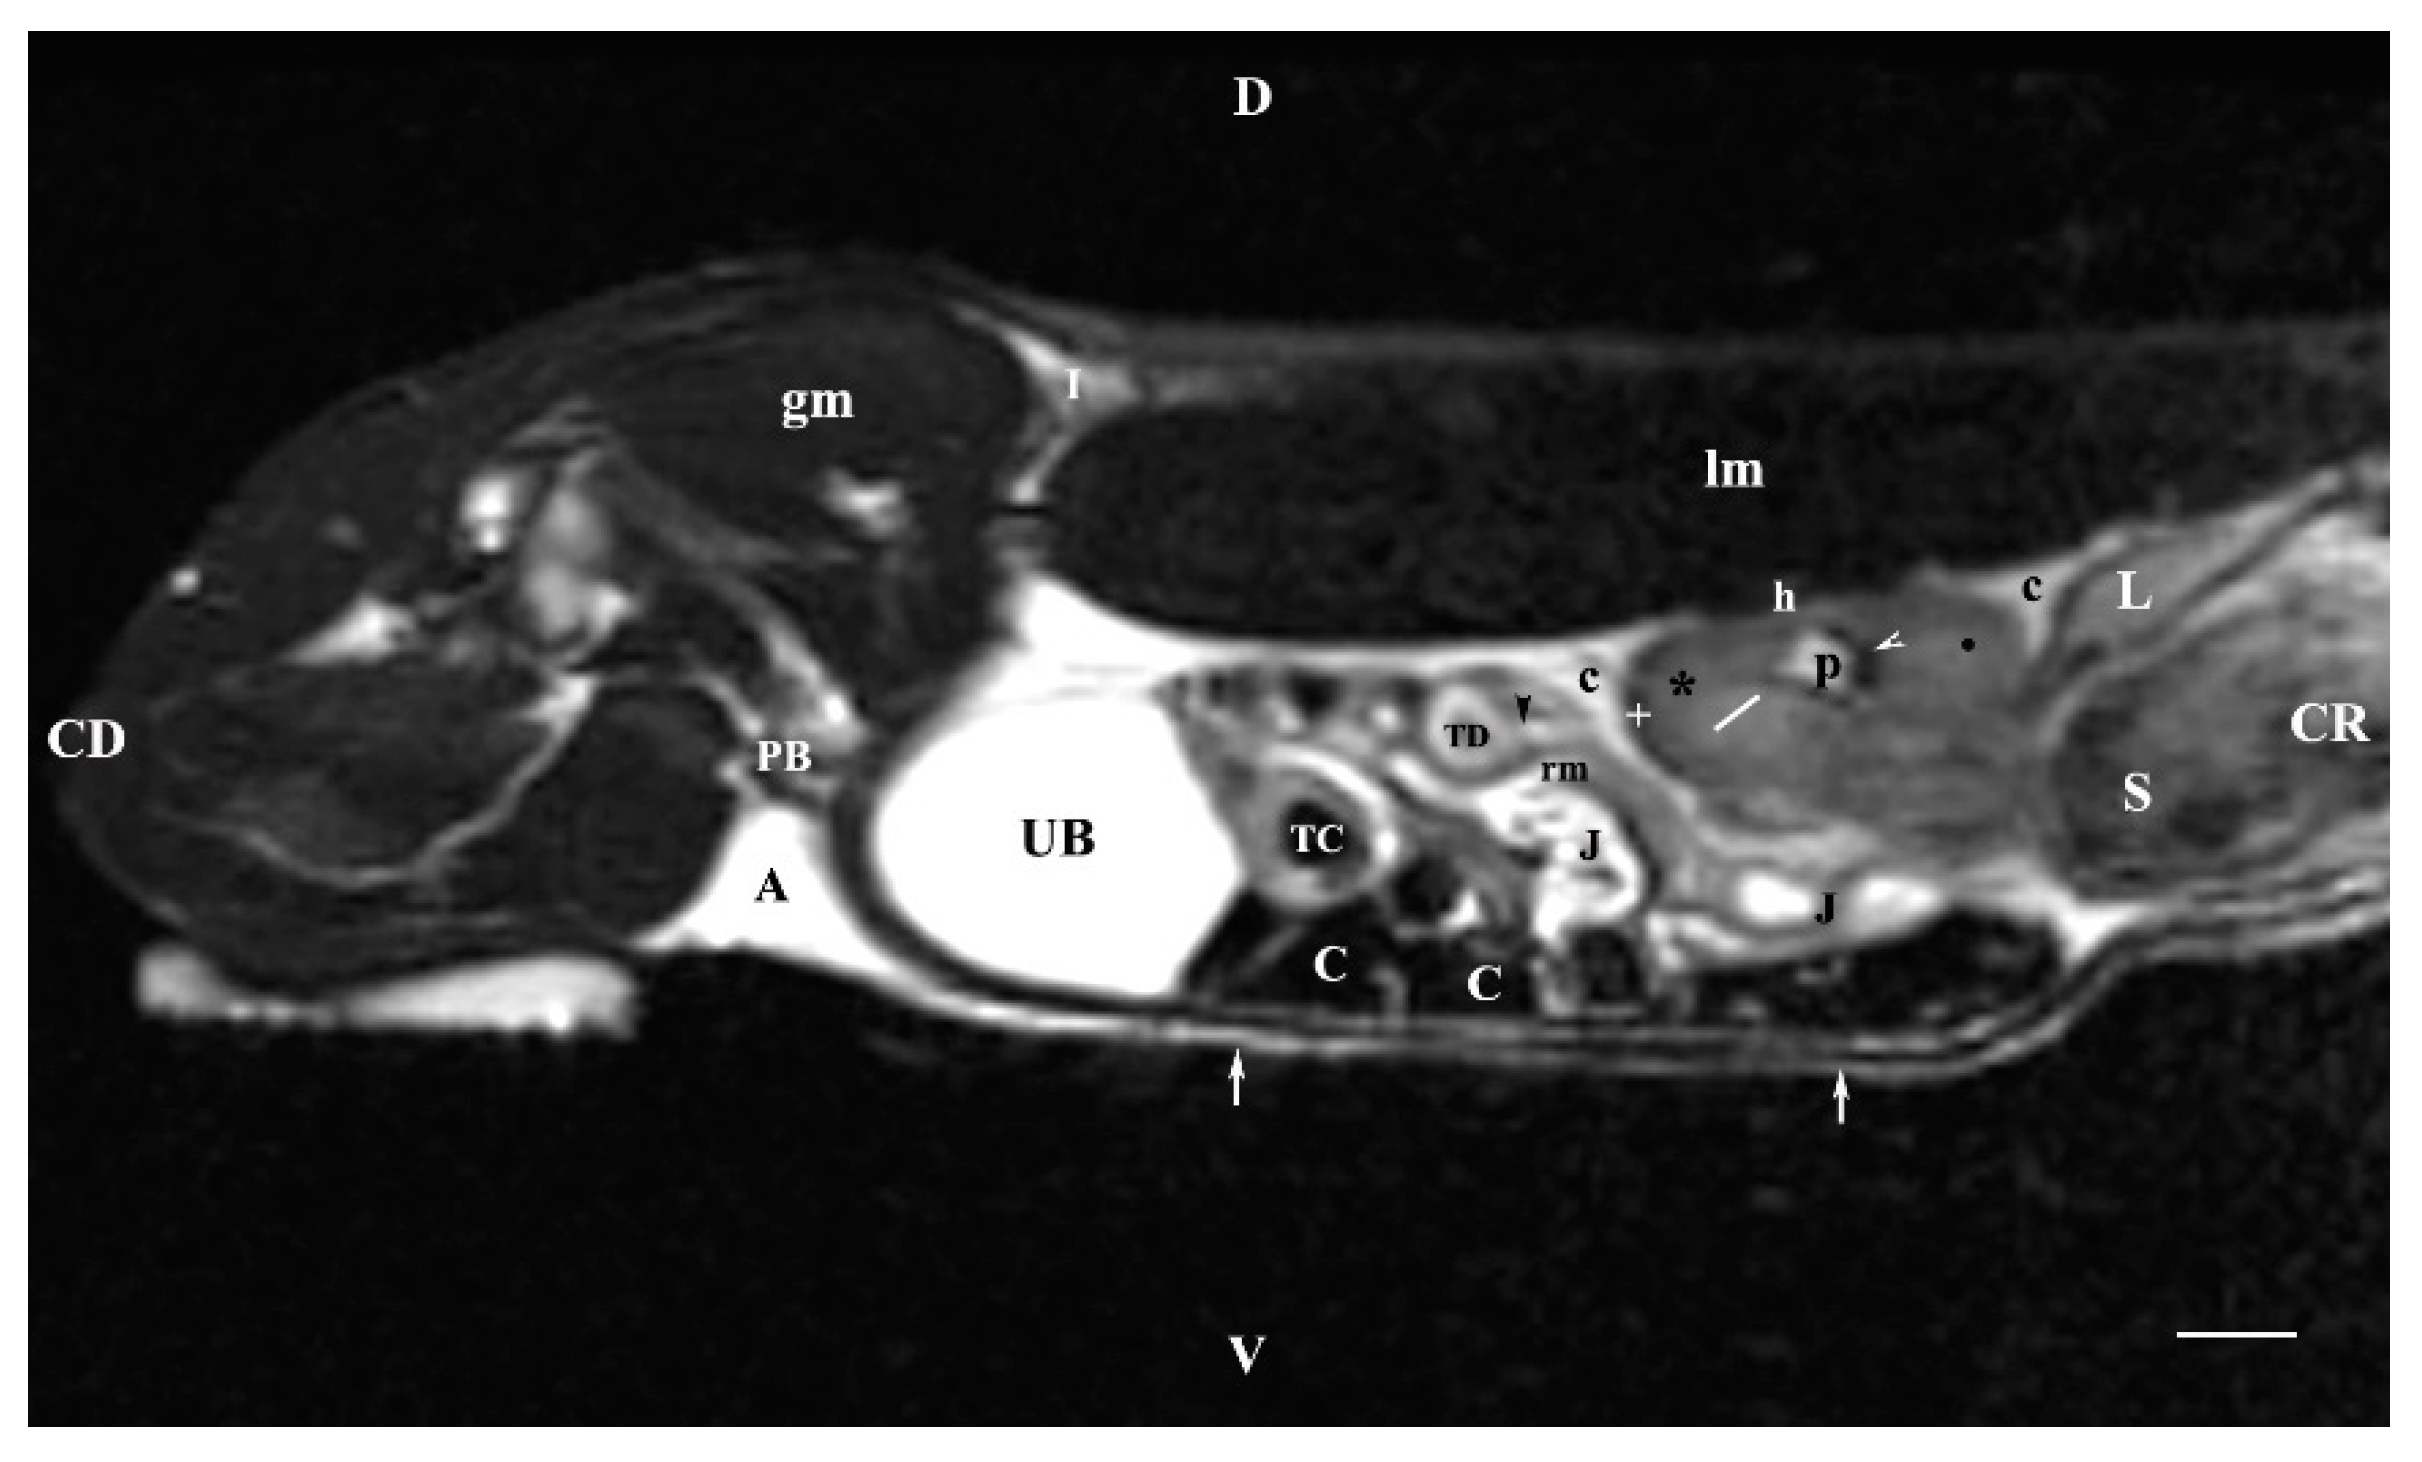

3.2. Sagittal MRI